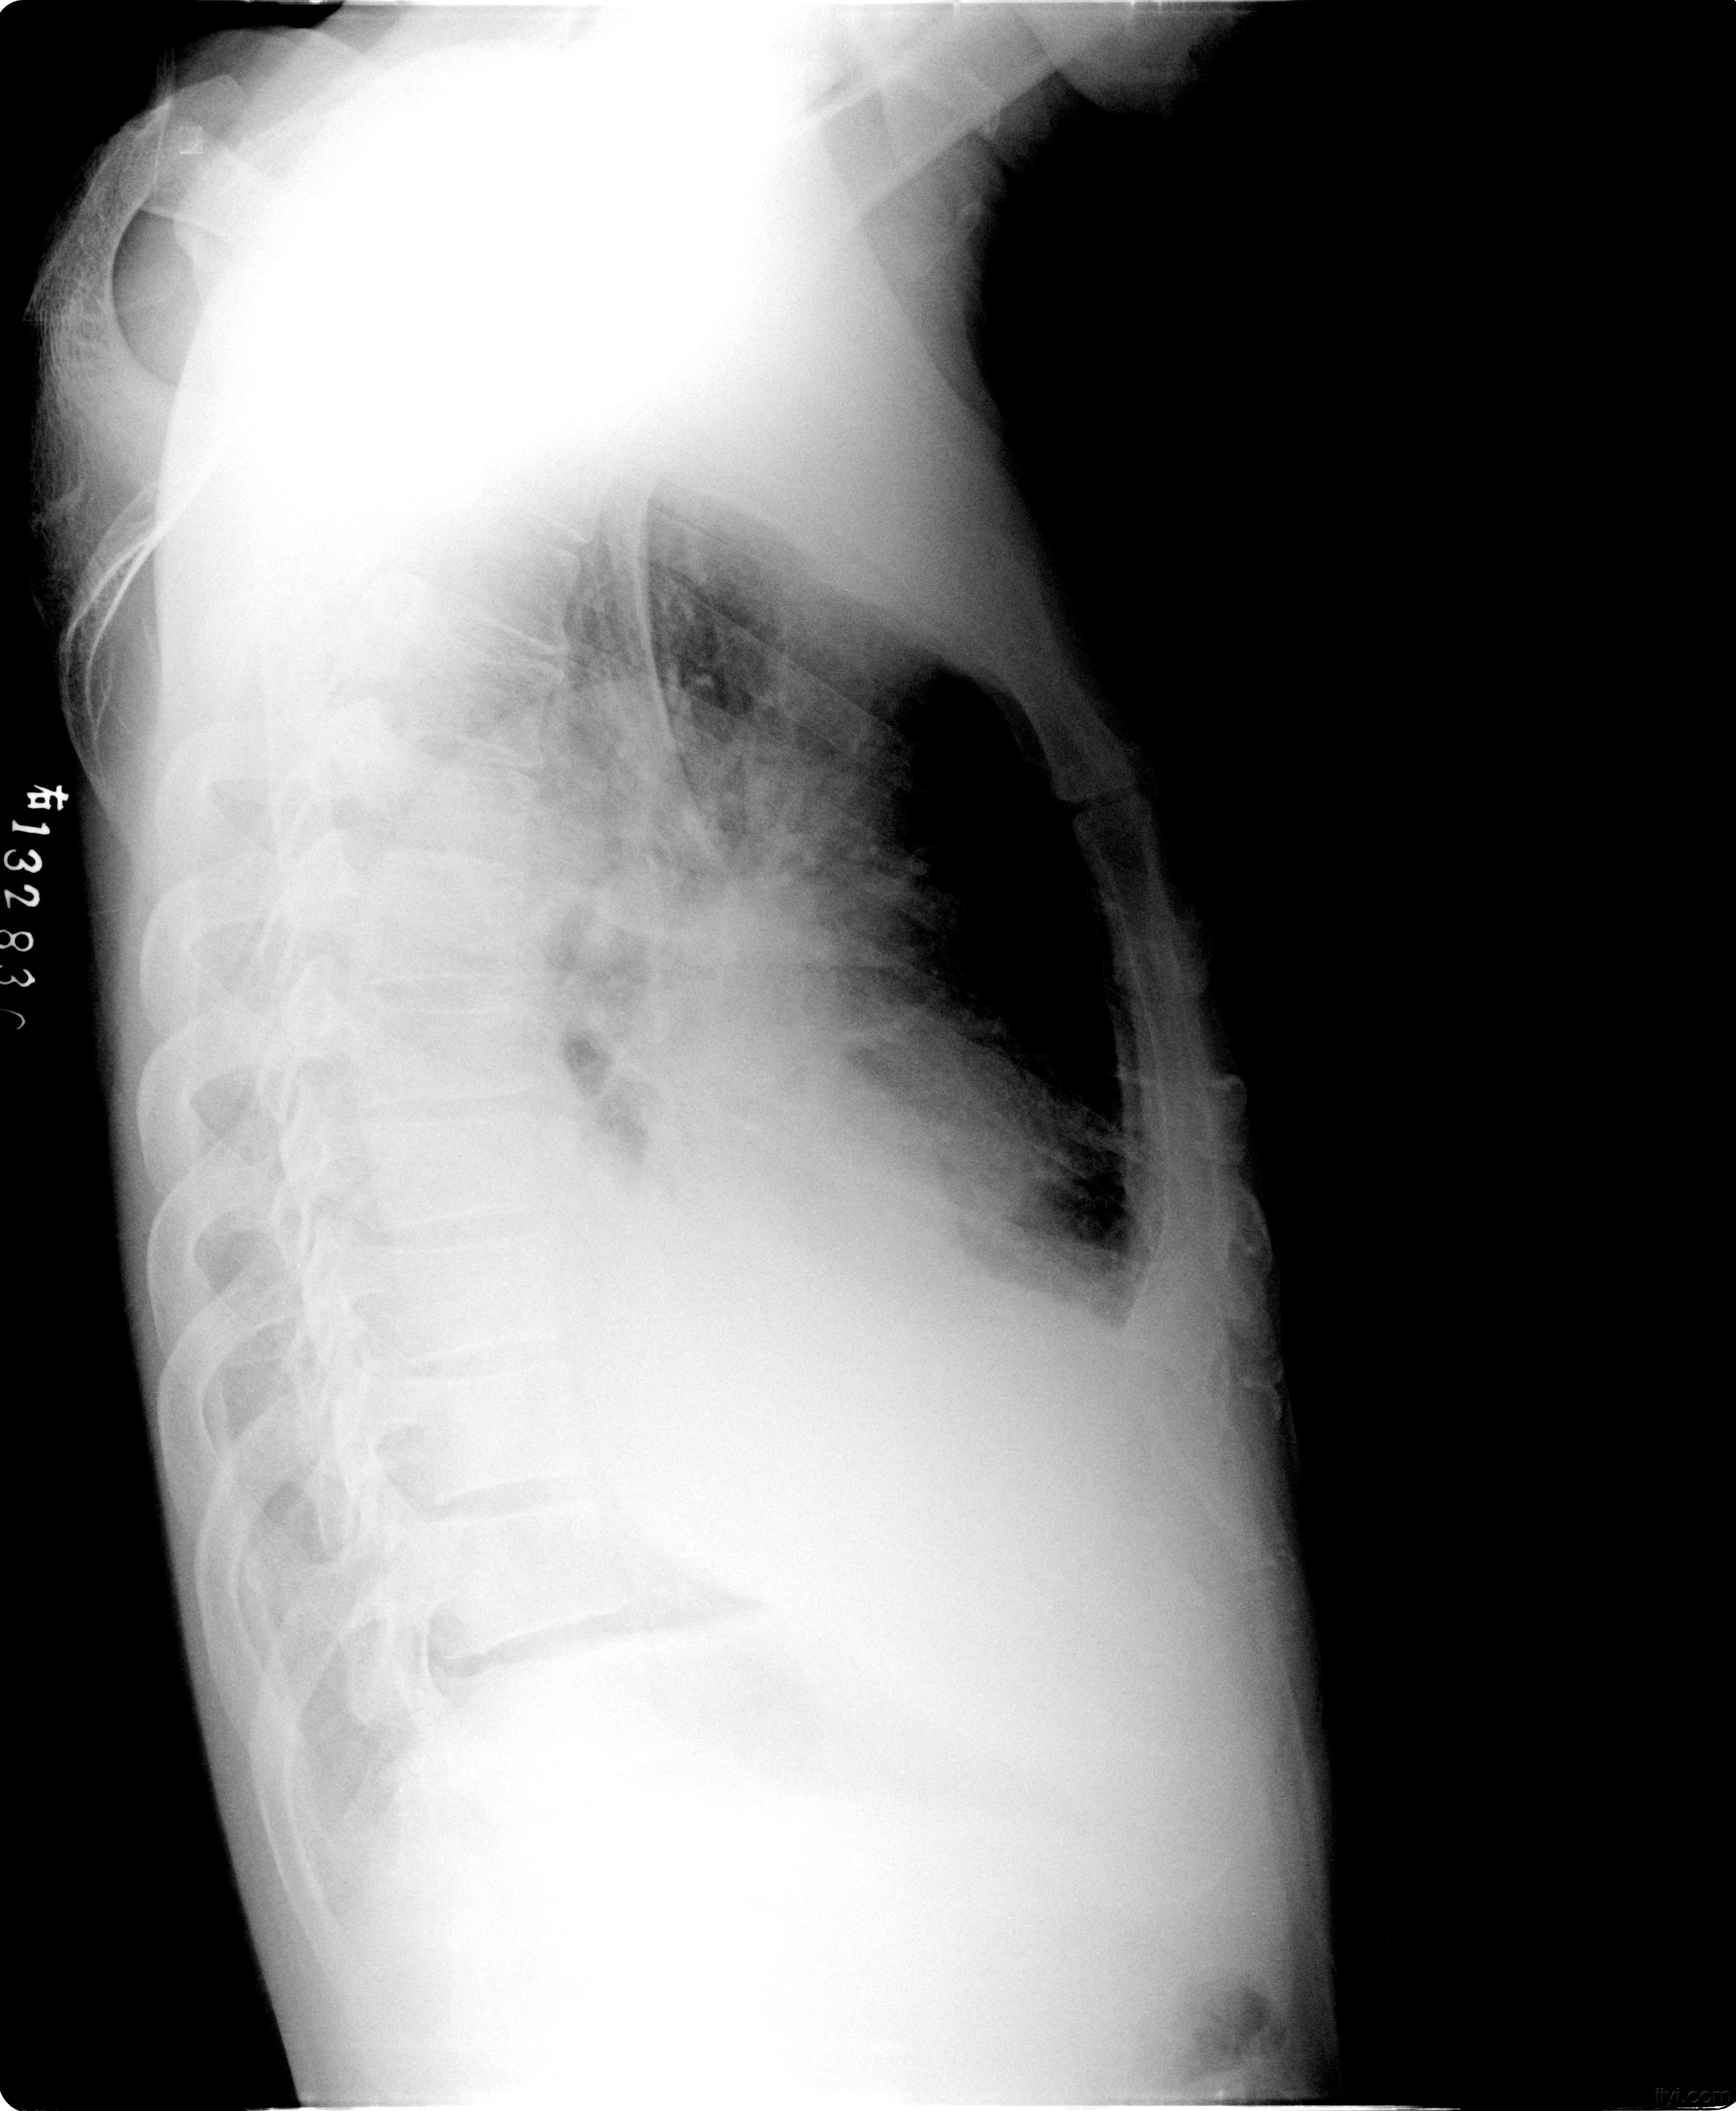

kerleyb线胸片

教学病例13胸片阅读kerleyb线讨论在9楼

请老师帮忙看看这张胸片的kerleyb线在哪

双侧,中心气道病变(白色箭头),下副裂积液(红色箭头)和kerley b线